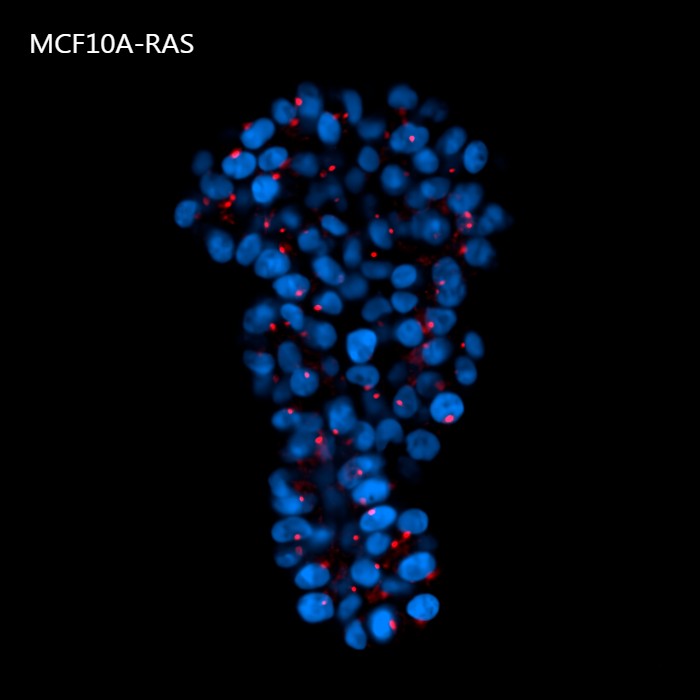

Figure 4 shows a maximum intensity projection (MIP) of 60 um Z-stack of non-malignant (A) and tumorigenic (B) acini. By providing homogeneous illumination over the entire 25 mm field of view (FOV), the X-Light V3 confocal spinning disk allowed us to analyze a large number of acini, reducing the number of images required to obtain robust data and, therefore, minimizing acquisition time.

B

Figure 4: MIP from 60 um Z-stack of non-malignant (A) and tumorigenic acini (B). Cells were cultured in 3D Matrigel suspensions and stained with pericentrin (red) and DAPI (blue). These images were acquired with a CFI Plan Apochromat Lambda D 20x air objective (20x, Nikon, 0.8 NA and 0.8 mm WD).

Using such an automated analysis pipeline, we have collected a wide range of information useful in understanding how mutated Ras receptors affect the proliferation and morphology of acini. As shown in Figure 8A, acinar structures from cultures of non-malignant breast cancer typically have round symmetrical shapes. On the other hand, the acini from malignant breast cancer cultures cause a deformation in the 3D architecture which causes the shape of the acini to be more elongated and deconstructed. Notably, the spheroids derived from the MCF10A K-Ras engineered line has a significant volume increase compared to the control line (Figure 8B). In fact, the transforming contribution of the k-Ras oncogene correlates with the increase in the cellular proliferative rate, and this causes an increase in volume already after 6 days in culture.

A

Figure 8: Representative MCF10A-CTR and MCF10A-RAS acini (A) and volume analysis (um3) (B). Cells were cultured in 3D Matrigel suspensions and stained with pericentrin (red) and DAPI (blue). This image was acquired with a CFI Plan Apochromat Lambda D 20x air objective (20x, Nikon, 0.8 NA and 0.8 mm WD). Volume comparison between MCF10A-CTR and MCF10A-RAS acini (B).